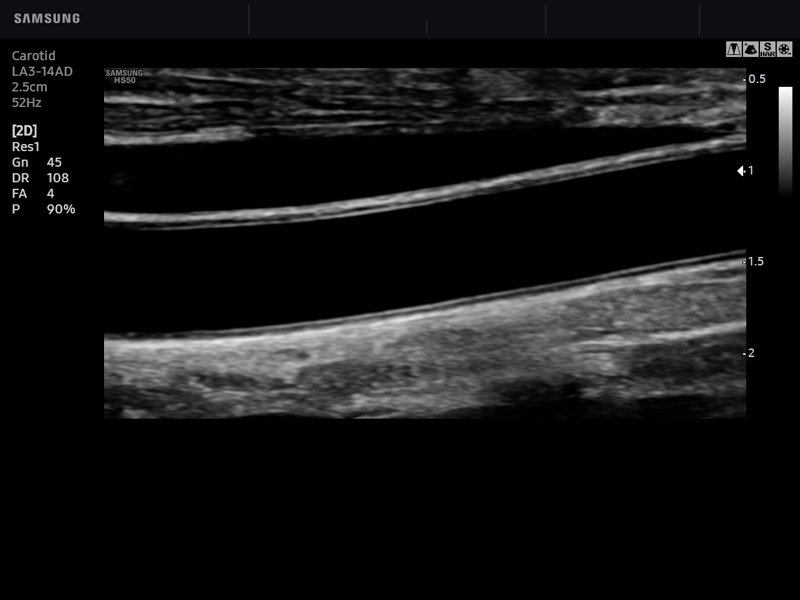

Common carotid artery, B-mode

Common carotid artery, B-mode (echogramm №767)

[RU] Ultrasound image №767: Common carotid artery (CCA) in B-mode (linear probe 3-14 MHz).

Echogramm was received by ultrasound scanner HS50 (available for sale).